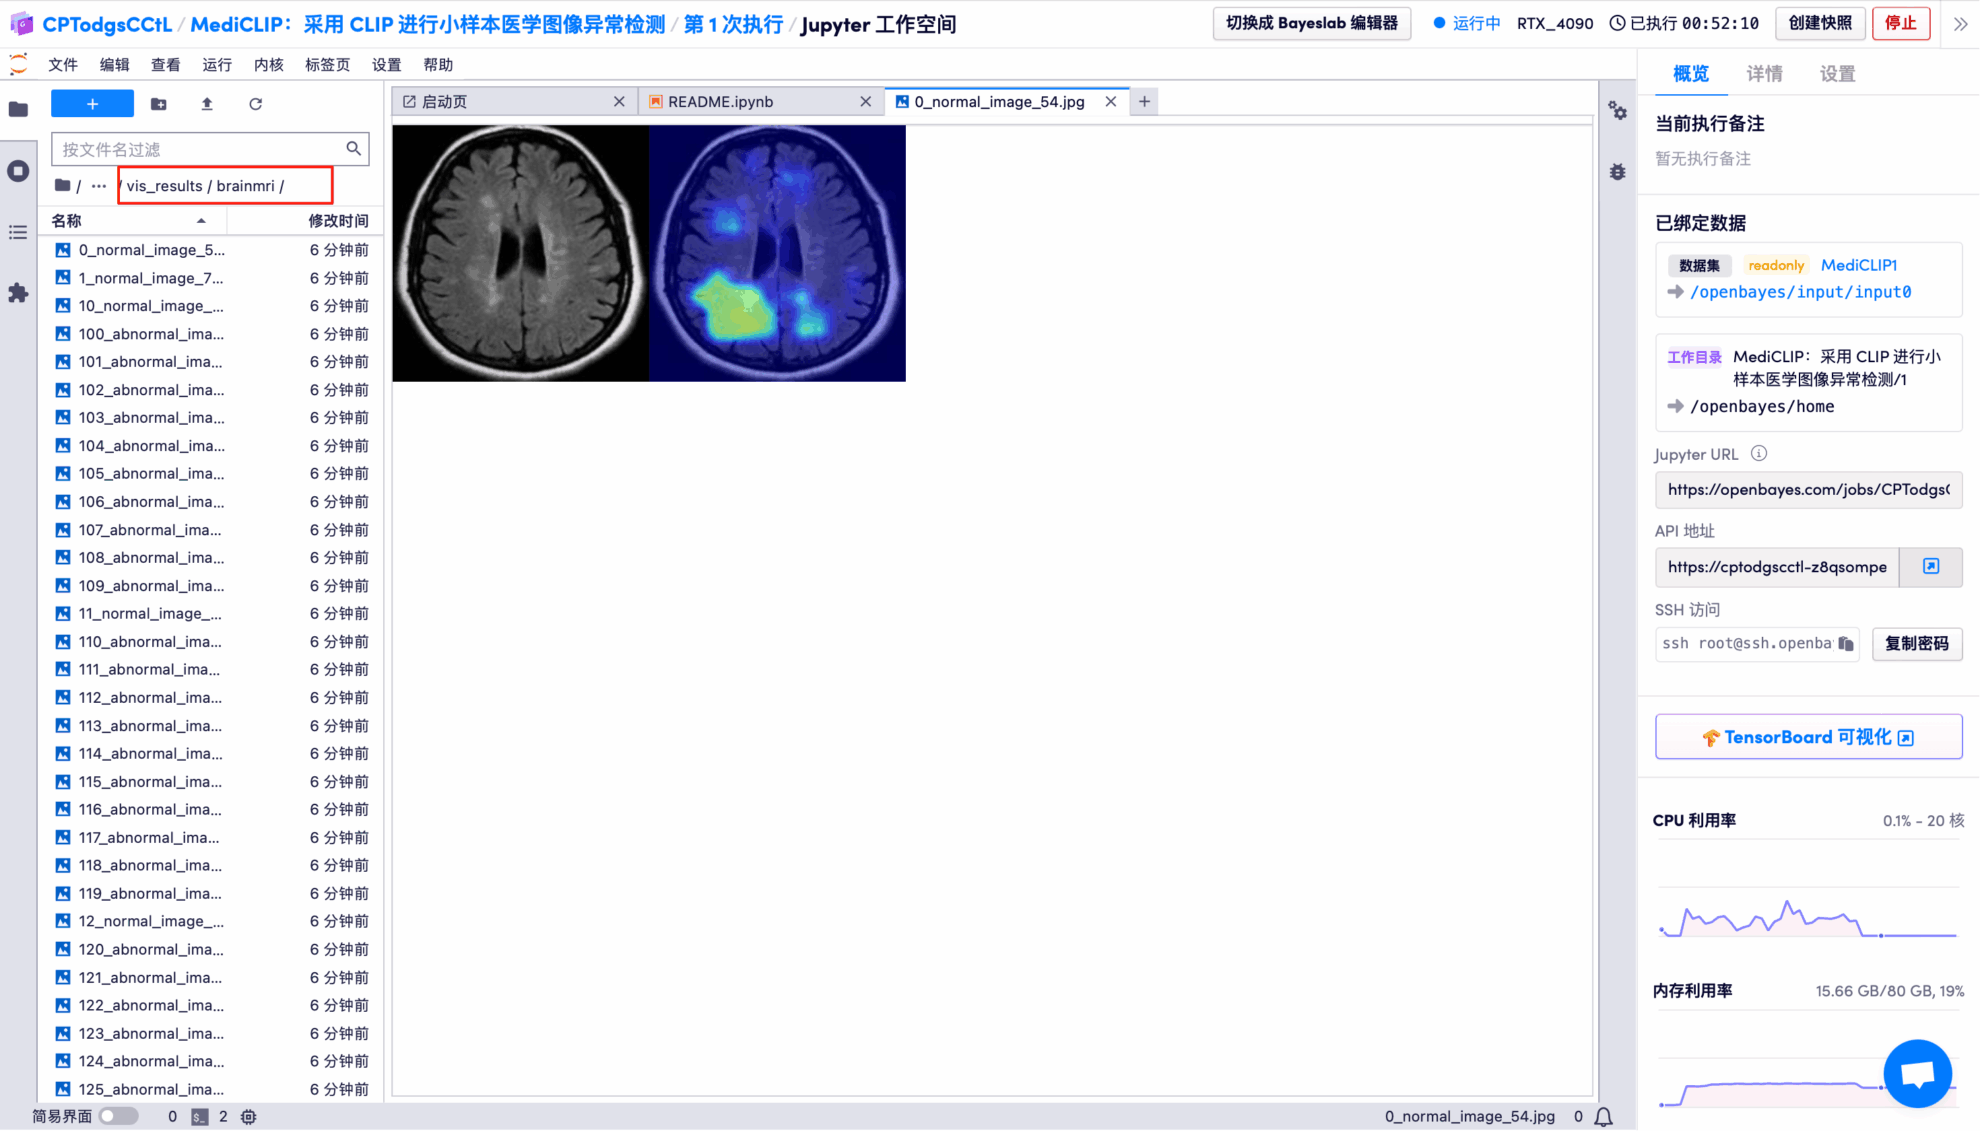

The output results show that the model performs very well in binary classification of images on the BrainMRI test set, with an AUROC of 0.9424 (close to a full score of 1).

The model's visual detection results for each test image are saved to the openbayes//home/MediCLIP/vis_result directory by default. The specific location is shown in the figure below:

Randomly open a test result picture, which is clearly and intuitively displayed:

* Left: Original brain image

* Right: Highlighted "abnormal area"